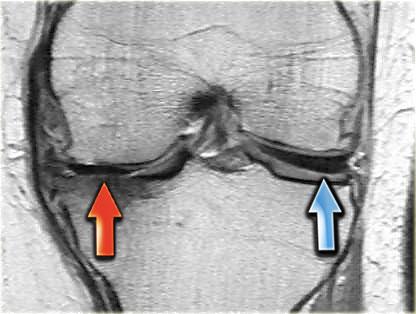

Bên trái là ba lát cắt coronal PD liên tiếp:

-

Rách bó dây chằng bên trong sâu (mũi tên vàng).

Bong mảnh xương ở mặt ngoài đầu gần xương chày, tức là gãy xương Segond (mũi tên đỏ). -

Lưu ý mảnh sụn chêm phía trong bị di lệch.

Điều này cho thấy còn có thêm rách dạng quai xô (bucket handle tear). -

Ngoài rách dạng quai xô (mũi tên xanh phía trong), còn có một đường rách ngang khó nhận thấy ở phần ngoại vi của sụn chêm (mũi tên xanh phía ngoài).

Đường rách ngang này được thể hiện rõ hơn trên các hình ảnh khác (không trình bày ở đây).